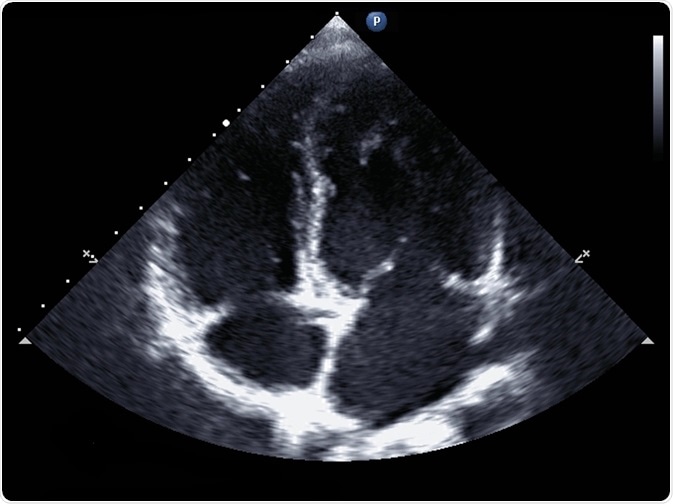

In echocardiography, ultrasound waves are used to produce a 2-dimensional image of the heart. It is a very safe examination with no side effects. It allows the physician to assess heart function. The test may be useful to diagnose a patient who has reported symptoms such as shortness of breath or chest pain.

In standard echocardiography, a black and white image is produced in real-time, allowing for an accurate assessment of chamber size and thickness.

The size of each ventricle can also be calculated to diagnose myocardial hypertrophy, a heart enlargement that more commonly affects the left ventricle and occurs in diseases such as heart failure. The 2-dimensional moving picture of the heart also allows the assessment of cardiac valve function and the identification of congenital disabilities.